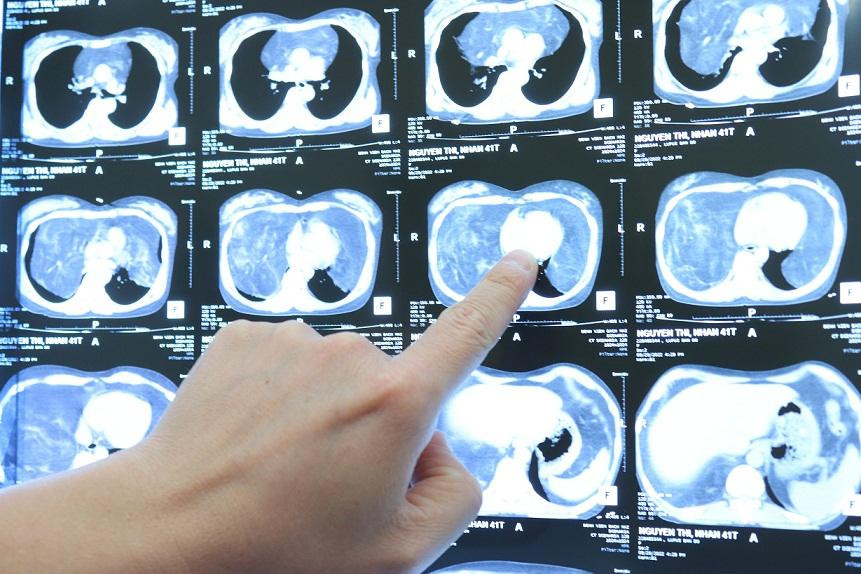

Chị Hoa bị bệnh Lupus (một loại bệnh lý gây ra do rối loạn đáp ứng miễn dịch) nhiều năm nay vẫn định kỳ đi khám và điều trị tại Bệnh viện Bạch Mai. Gần đây chị thấy đau tức ngực, khó thở nhiều, triệu chứng ngày càng nặng. Bác sỹ cho chụp cắt lớp thì phát hiện chị có u trung thất lớn, trọng lượng khoảng 4 kg, chiếm phần lớn thể tích lồng ngực. Khối u lớn làm giảm thể tích trường phổi hai bên, gây chèn ép tim và các mạch máu lớn trên nền bệnh lý mãn tính gây không ít lo ngại cho quá trình điều trị. Sau khi hội chẩn liên khoa Tim mạch, Dị ứng, Gây mê hồi sức, Phẫu thuật lồng ngực để tìm phương án, các bác sĩ đã quyết định phẫu thuật để cắt bỏ khối u.

ThS.BS. Ngô Gia Khánh, Trưởng Khoa Phẫu thuật lồng ngực mạch máu - Bệnh viện Bạch Mai, người trực tiếp phẫu thuật cho bệnh nhân Hoa cho biết: Khối u là tổ chức mỡ, chiếm toàn bộ trung thất và phần dưới khoang màng phổi, ranh giới u tương đối rõ với các tổ chức xung quanh. Với trọng lượng sau khi cắt khoảng 4kg, khối u khổng lồ khiến hai phổi của bệnh nhân bị đẩy lên trên, ôm quanh tim và các mạch máu lớn. Đây chính là nguyên nhân dẫn đến việc bệnh nhân Hoa bị tức ngực, khó thở. Chia sẻ về độ phức tạp của ca phẫu thuật, ThS.BS. Gia Khánh cho biết: Khối u to, đường mổ lớn nên nguy cơ mất máu, đau sau mổ rất lớn. E kip gây mê và phẫu thuật đã phải phối hợp và theo dõi sát từng chỉ số huyết động trong mổ, phẫu tích, bảo tồn các cấu trúc mạch máu, thần kinh trong toàn bộ cuộc mổ để hạn chế mất máu mà vẫn lấy trọn khối u lớn, giải phóng hai phổi khỏi bị chèn ép.